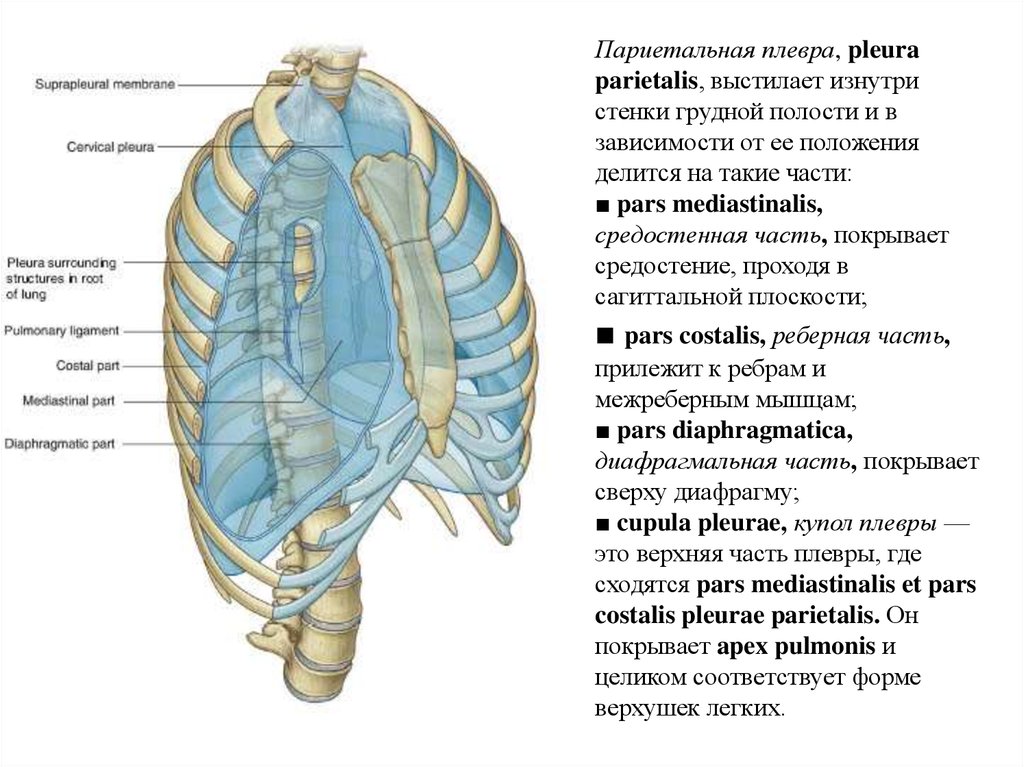

Анатомия межплеврального пространства